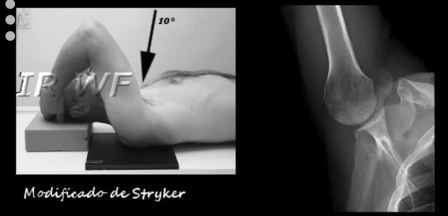

Ombro- Modificado de Stryker

Indicação de estudoEsta posição vai demonstrar uma deformidade chamada Hills -Sachs da cabeça do úmero.

Raio centralO raio central está inclinado 10° grau cranial e dirigido através do centro da axila para a cabeça do úmero.

Tamanho do filme - 24 x 30 cm - Transversal